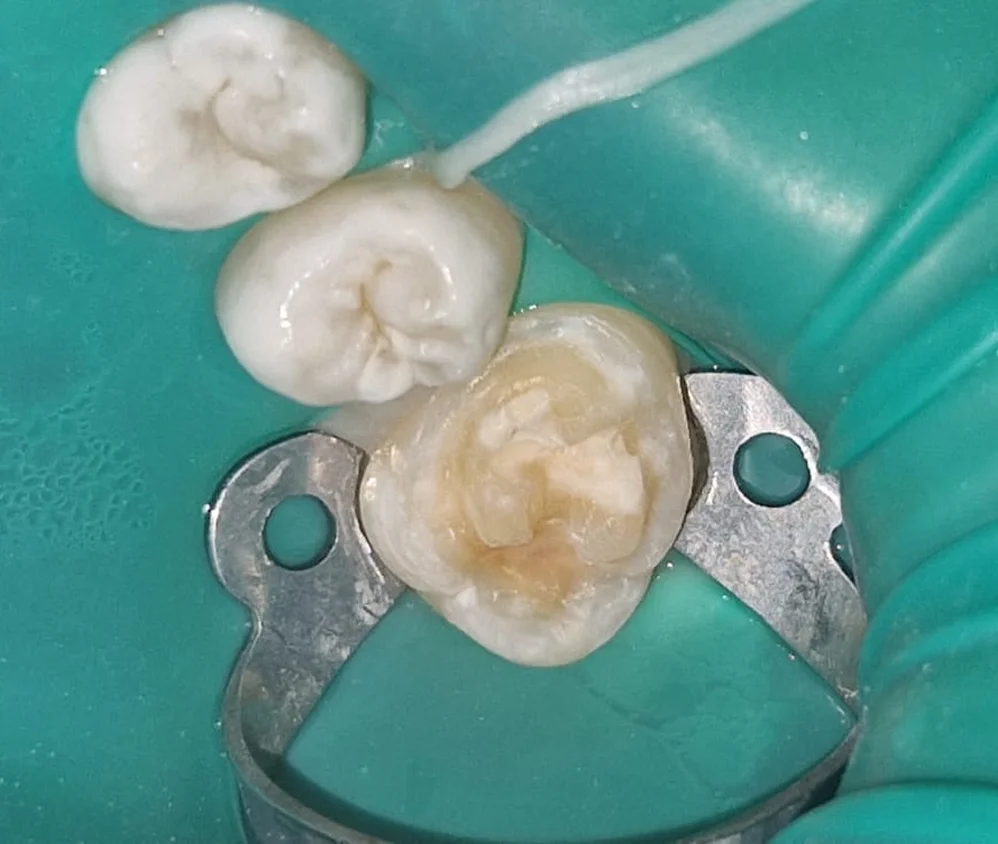

Работать с тканями с нарушенной минерализацией.

Адгезия к гипоминерализованной эмали и измененному дентину, выбор между прямой и непрямой реставрацией — с клиническим обоснованием.

Реставрация зубов с пороками твердых тканей: адгезия, материалы, протокол.

Особенности адгезии к гипоминерализованной эмали и изменённому дентину. Критерии выбора между прямой и непрямой реставрацией.